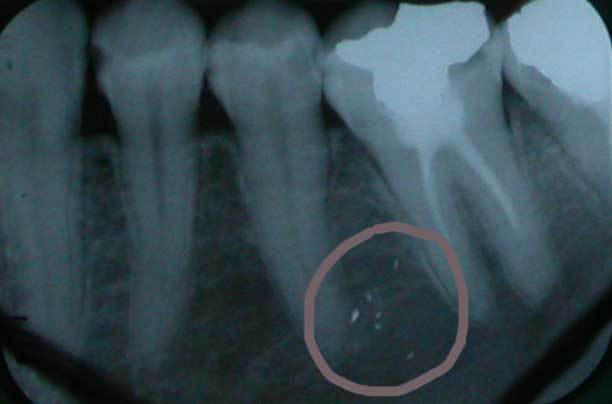

si vous voulez je joint radio on l'on peut soupçonner un tatouage a l'amalgame (c'est veridique):étonné?

Dscn1246 tc9gkv - Eugenol